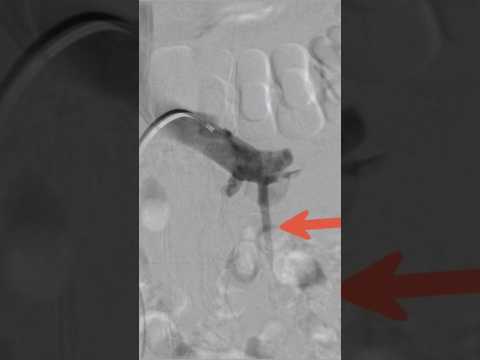

Varicocele embolization live case - Step 13 #nosurgery | Dr. Gaurav Gangwani

Varicocele Embolisation Angiography (venogram) of left gonadal vein in a man suffering from